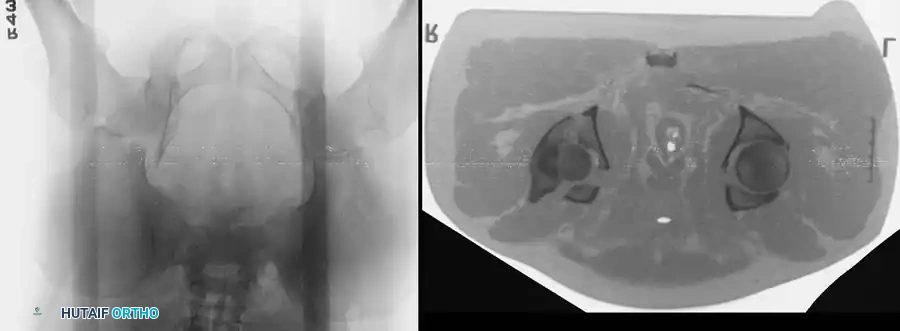

Fig. 53-4 Anteroposterior pelvic radiograph ( A ) and CT scan ( B ) of irreducible hip dislocation with posterior wall acetabular fracture. Posterior wall fragment is incarcerated, blocking reduction.

If closed reduction under conscious sedation or general anesthesia fails, urgent open reduction is mandated. A rapid, fine-cut (2-3 mm) Computed Tomography (CT) scan should be obtained to identify the incarcerating fragment—often a rotated posterior wall fragment or an intra-articular osteochondral loose body. Prolonged dislocation exponentially increases the risk of femoral head osteonecrosis and irreversible sciatic nerve ischemia.